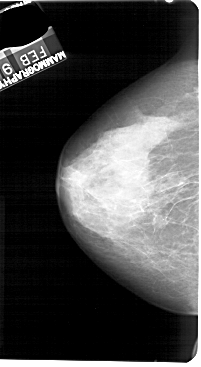

A_1270_1.RIGHT_CC

RIGHT_CC LINES 4831 PIXELS_PER_LINE 2731 BITS_PER_PIXEL 12 RESOLUTION 43.5 OVERLAY